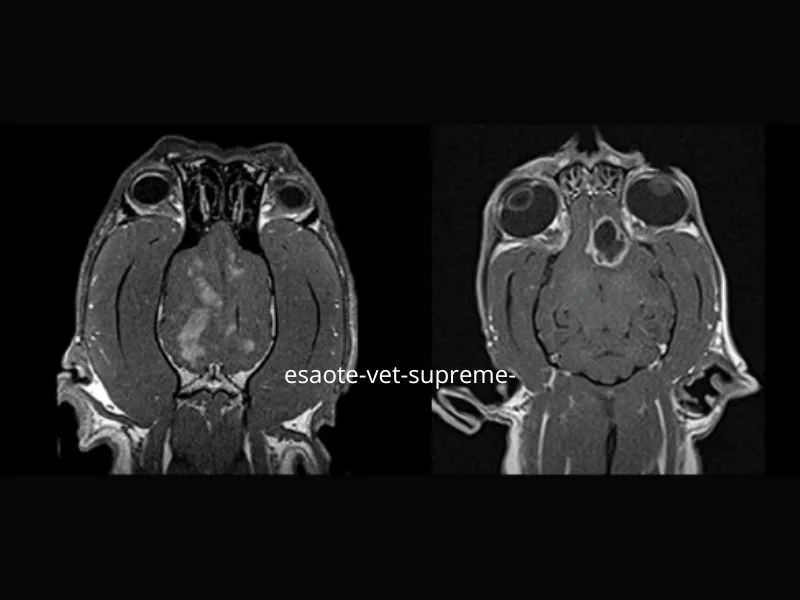

Supreme vet-mr – Dorsal T1W slices with Contrast Uptake in two dogs with pathological brain